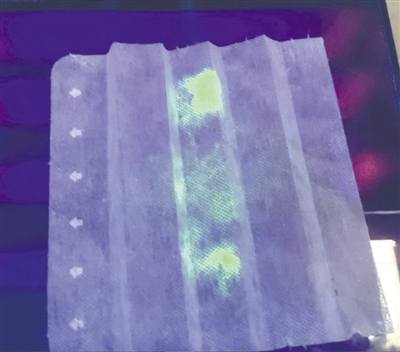

新冠病毒样本在紫外线照射下会发光。

图片来源:《日本时报》网站

去年2月,该研究小组向雌性鸵鸟注射了灭活新冠病毒,成功地从它们产下的蛋中提取了大量抗体。接着,该小组开发了一种特殊的过滤器,可将其放置于口罩内。在受试者佩戴口罩8小时后,研究小组取出过滤器,喷上含有鸵鸟蛋抗体的荧光染料,如果存在新冠病毒,过滤器在紫外线照射下会发光。

研究团队对32名感染新冠病毒的患者进行了长达10天的观察后发现,感染者佩戴的所有口罩在紫外线照射下都会发光,但随着时间的推移和病毒载量的减少,口罩会褪色。